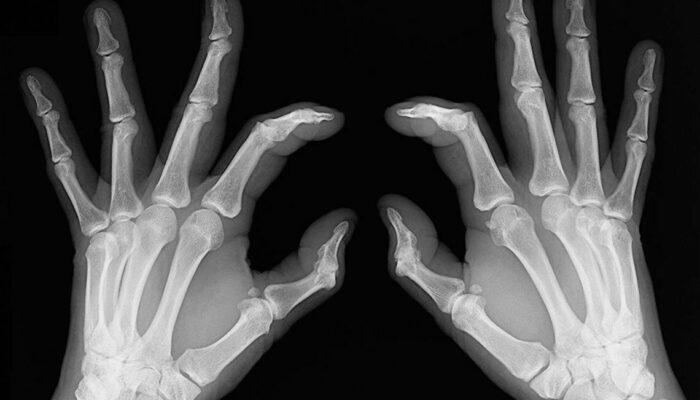

- Bone deformation: Arthritis also attacks the bones and makes them crooked and stiff. Look out for signs of any subtle changes in your joints and test them for pain levels.

- Inflammation: Sometimes rheumatoid arthritis symptoms show chronic flare up and can lead to swollen joints and inflammation. They are also symptomatic of lupus, so do consult your doctor before getting yourself treated for rheumatoid arthritis.